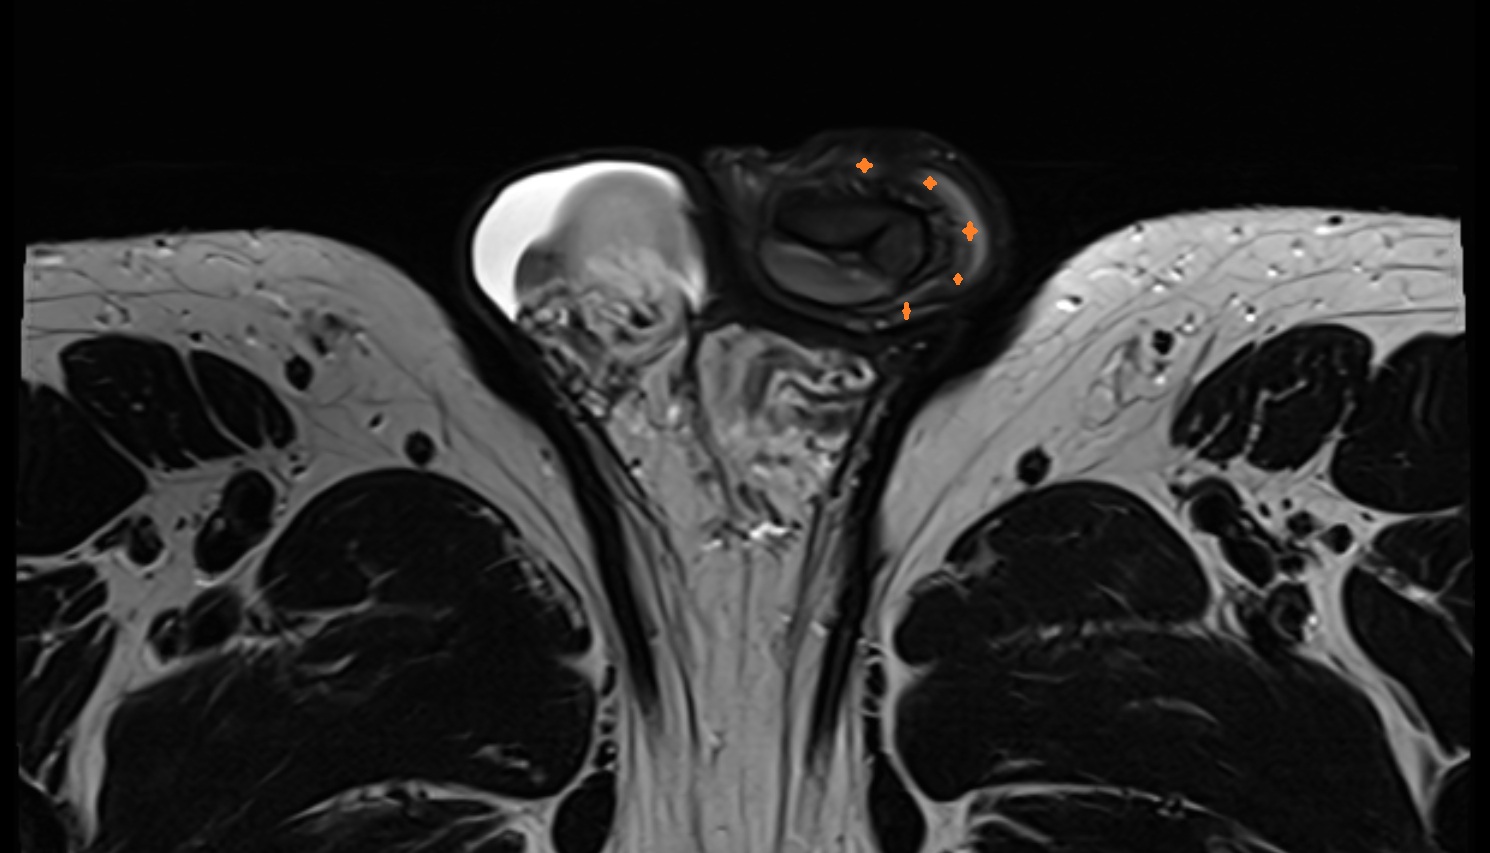

- Peripheral zone of prostate

- Anterior Fibromuscular Stroma of prostate

- Central zone of prostate

- Transitional zone of prostate